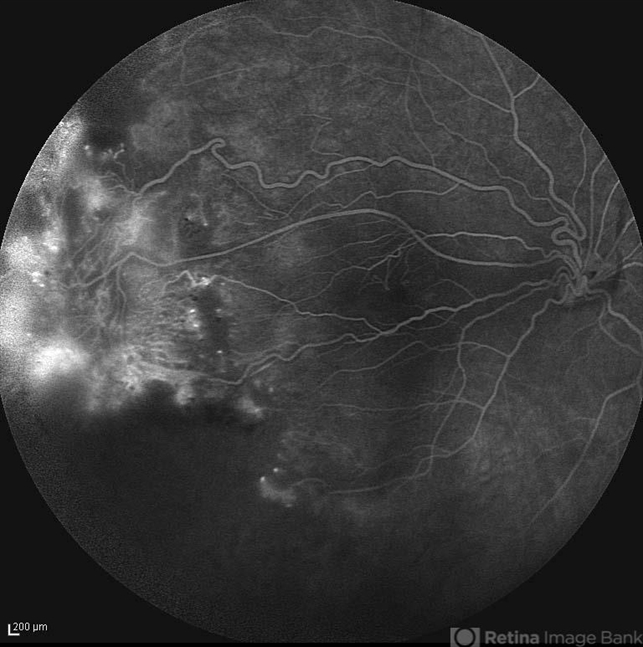

- optic disc hypoplasia, fibrovascular proliferation, peripheral retinal nonperfusion

- Late FA image of the right eye of a 24-year-old woman with peripheral retinal nonperfusion and fibrovascular proliferation associated with optic disc hypoplasia; visual acuity of 20/50. Her brother and sister were also involved with the same ocular disorder.